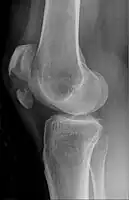

Vertical patella fracture